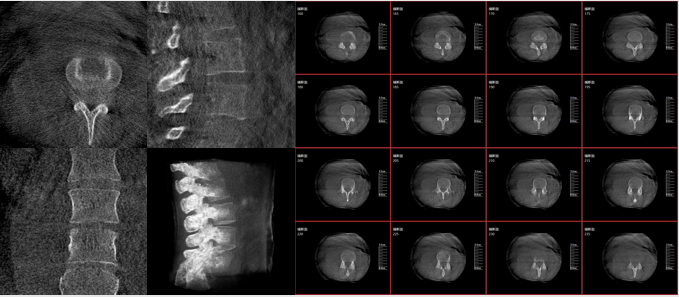

而三維影像的MPR圖像組可以通過不同平面的切分,使成像區內更豐富的信息得以呈現。尤其是二維影像無法涉及的橫斷面,提供了另一個空間維度的信息量。

術中三維C臂影像

術中三維C臂影像帶來的更加豐富的信息,可以作為醫生手術執行的判斷基礎,以及手術操作后實時的影像判斷依據,從而保障手術效果。

在既往的手術中可能會出現這樣的情況:術后在影像科CT檢查中發現某個手術效果需要調整,這時往往需要返臺、翻修等才能解決。而術中三維C臂提供的術中三維影像功能可以將這一步驟合并至手術流程中,有效地降低醫患雙方的風險,為手術保駕護航。